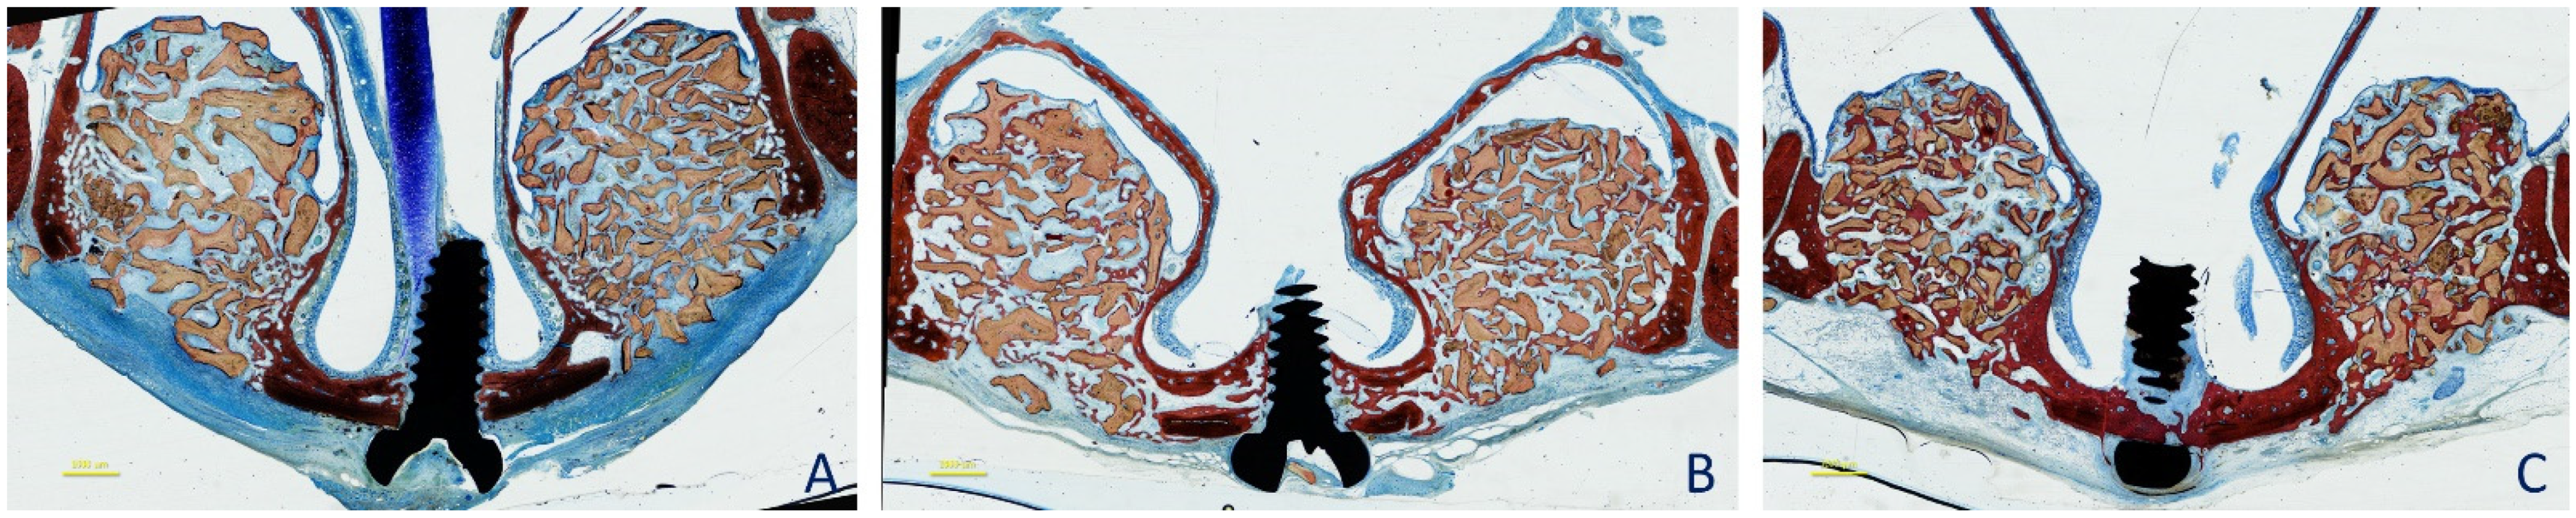

2.3. Surgical Procedures

2.5. MicroCT Evaluations